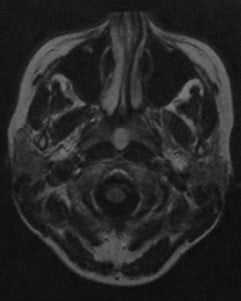

МРТ без контрастного усиления. На Т2-взвешенном изображении визуализируется киста Торнвальдта, расположенная по передней срединной линии в крыше носоглотки между брюшками длинной мышцы шеи. Содержимое кисты обычно гиперинтенсивно на Т2-взвешенном изображении.

Т1 -взвешенное изображение после введения гадолиния. Здесь содержимое кисты выглядит изо- или гипоинтенсивно по отношению к мышце. Гиперинтенсивное кольцо вокруг кисты представляет собой стенку кисты и усиленную слизистую оболочку глотки после введения гадолиния (стрелка)